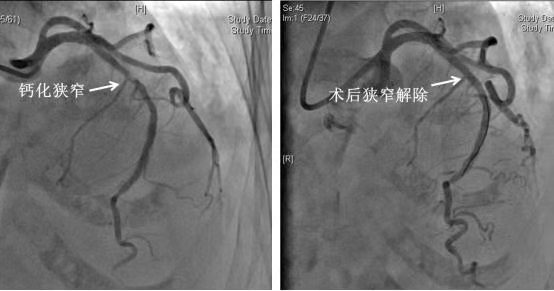

图3 冠脉旋磨+支架植入术前(左)和术后(右)对比

随后,在翟彦龙技师的配合下,为患者进行了IVUS检查,提示患者左前降支存在360°环形钙化,伴重度狭窄,最小管腔面积仅有1.9mm²。在医学上,环形钙化必须通过冠脉旋磨术才能得到有效治疗,冠脉旋磨术就是利用每秒钟15万转的高速旋磨头对钙化病变进行打磨(图2),以便于随后球囊、支架通过。患者在接受冠脉旋磨术后顺利植入1枚药物洗脱支架。手术过程顺利,耗时不足1小时,患者全程清醒,无任何痛苦,术后仅在右手腕处留有一个约米粒大小的穿刺点,术后就能够坐起并下地活动,术后患者未再发作胸痛、背痛等症状,左前降支原来的狭窄已经解除(图3),患者再也不需要含服硝酸甘油了,睡眠和饮食都得到了明显改善,并于3天后顺利出院。出院时患者家属对我院的整个治疗过称给予了高度的评价,并真挚感谢心脏内科团队为老人重获“心”生。真正体现了微创、快速、安全及准确的救治理念。